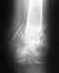

Мне 28 лет. Травма 13.12.08 - перелом н/3 обеих костей голени при неудачном приземлении с парашютом; 17.12.08 выполнен остеосинтез б/б кости пластинкой; 17.03.08 - снят гипс, сращение имеется. Только через 3 месяца после операции выяснилось, что операция сделана криво - имеется смещение в боковой проекции. Сейчас прохожу восстановительное лечение, боли в области перелома отсутствуют. Подскажите пожалуйста, как быть? Оставить всё как есть или ломать по новой?P.S. Есть большое желание продолжить прыжки с парашютом.

Рентгенограмма когда сделана?

Покажите сегодняшние снимки.